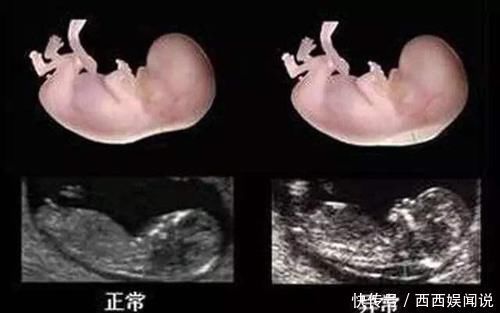

NT检查是最早的排畸检查,主要评估胎儿唐氏综合征的风险,准确率很高。

“NT”指的是颈后透明层,在产检结果中会有一个数值,但这个数值并不是越小越好,而是有正常范围,低于3毫米就表示胎儿正常。